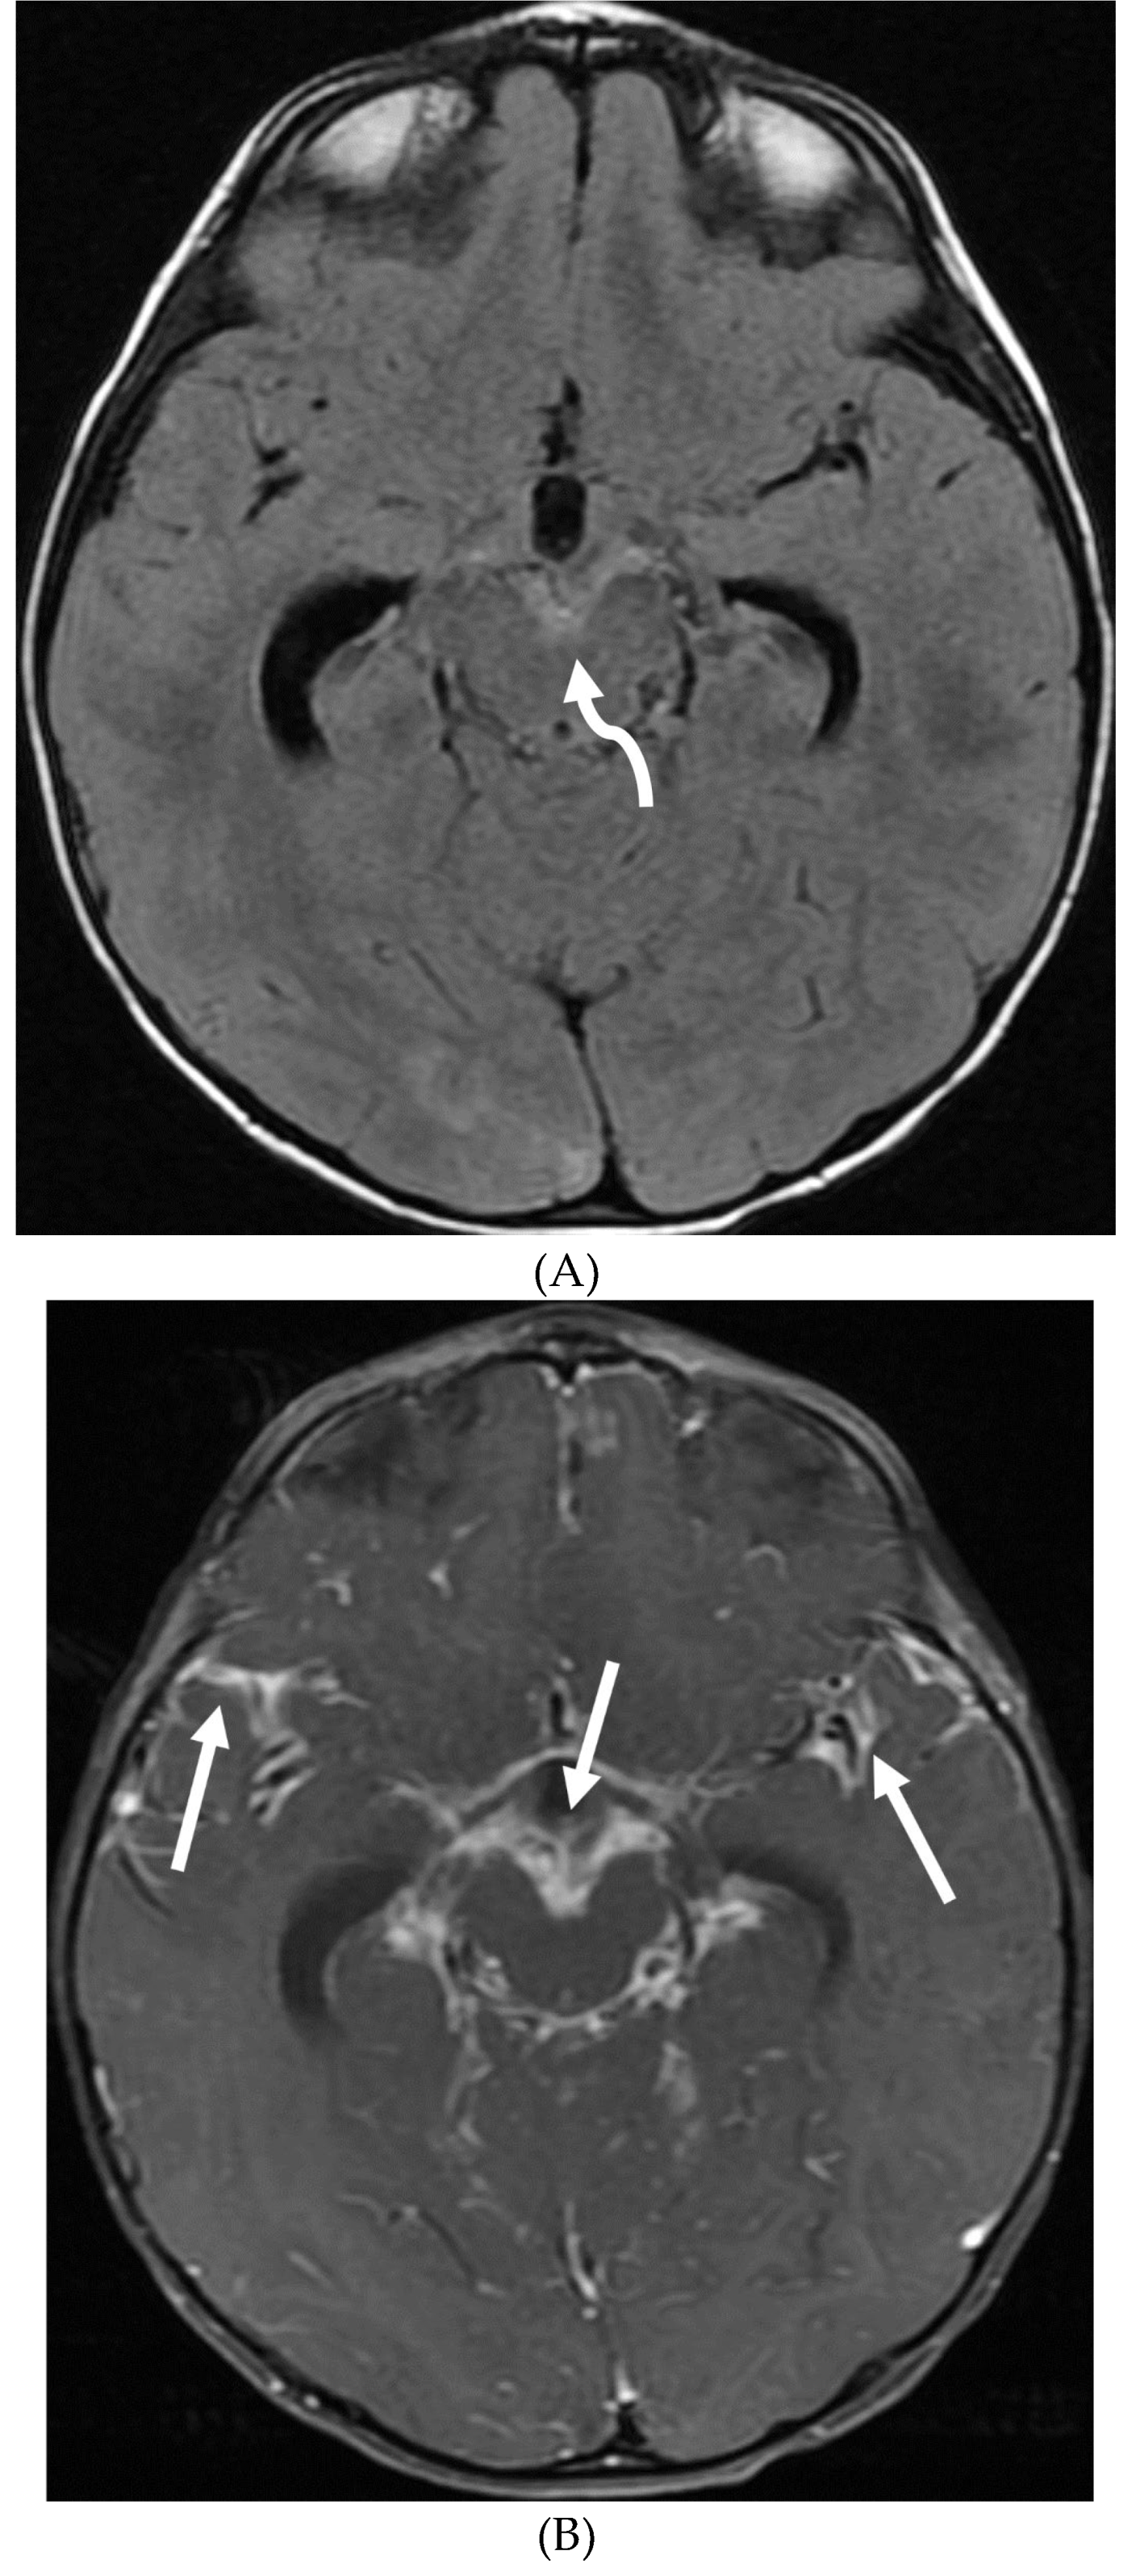

TUBERCULOSIS

- Chiang SS, Khan FA, Milstein MB, Tolman AW, Benedetti A, Starke JR, et al. Treatment outcomes of childhood tuberculous meningitis: a systematic review and meta-analysis. Lancet Infect Dis. (2014) 14:947–57. [CrossRef]

- Dian S, Hermawan R, van Laarhoven A, Immaculata S, Achmad TH, Ruslami R, Anwary F, Soetikno RD, Ganiem AR, van Crevel R. Brain MRI findings in relation to clinical characteristics and outcome of tuberculous meningitis. PLoS One. 2020 Nov 13;15(11):e0241974. PMID: 33186351; PMCID: PMC7665695. [CrossRef]

- Krishnan N, Renganathan L. Tuberculous meningitis sequelae as basal cisternal calcifications. J Pediatr Neurosci. 2016 Jan-Mar;11(1):86-7. PMID: 27195045; PMCID: PMC4862301. [CrossRef]

- Khatri GD, Krishnan V, Antil N, Saigal G. Magnetic resonance imaging spectrum of intracranial tubercular lesions: one disease, many faces. Pol J Radiol. 2018 Dec 29;83:e524-e535. PMID: 30800191; PMCID: PMC6384409. [CrossRef]

- Bomanji JB, Gupta N, Gulati P, Das CJ. Imaging in tuberculosis. Cold Spring Harb Perspect Med. 2015 Jan 20;5(6):a017814. PMID: 25605754; PMCID: PMC4448708. [CrossRef]